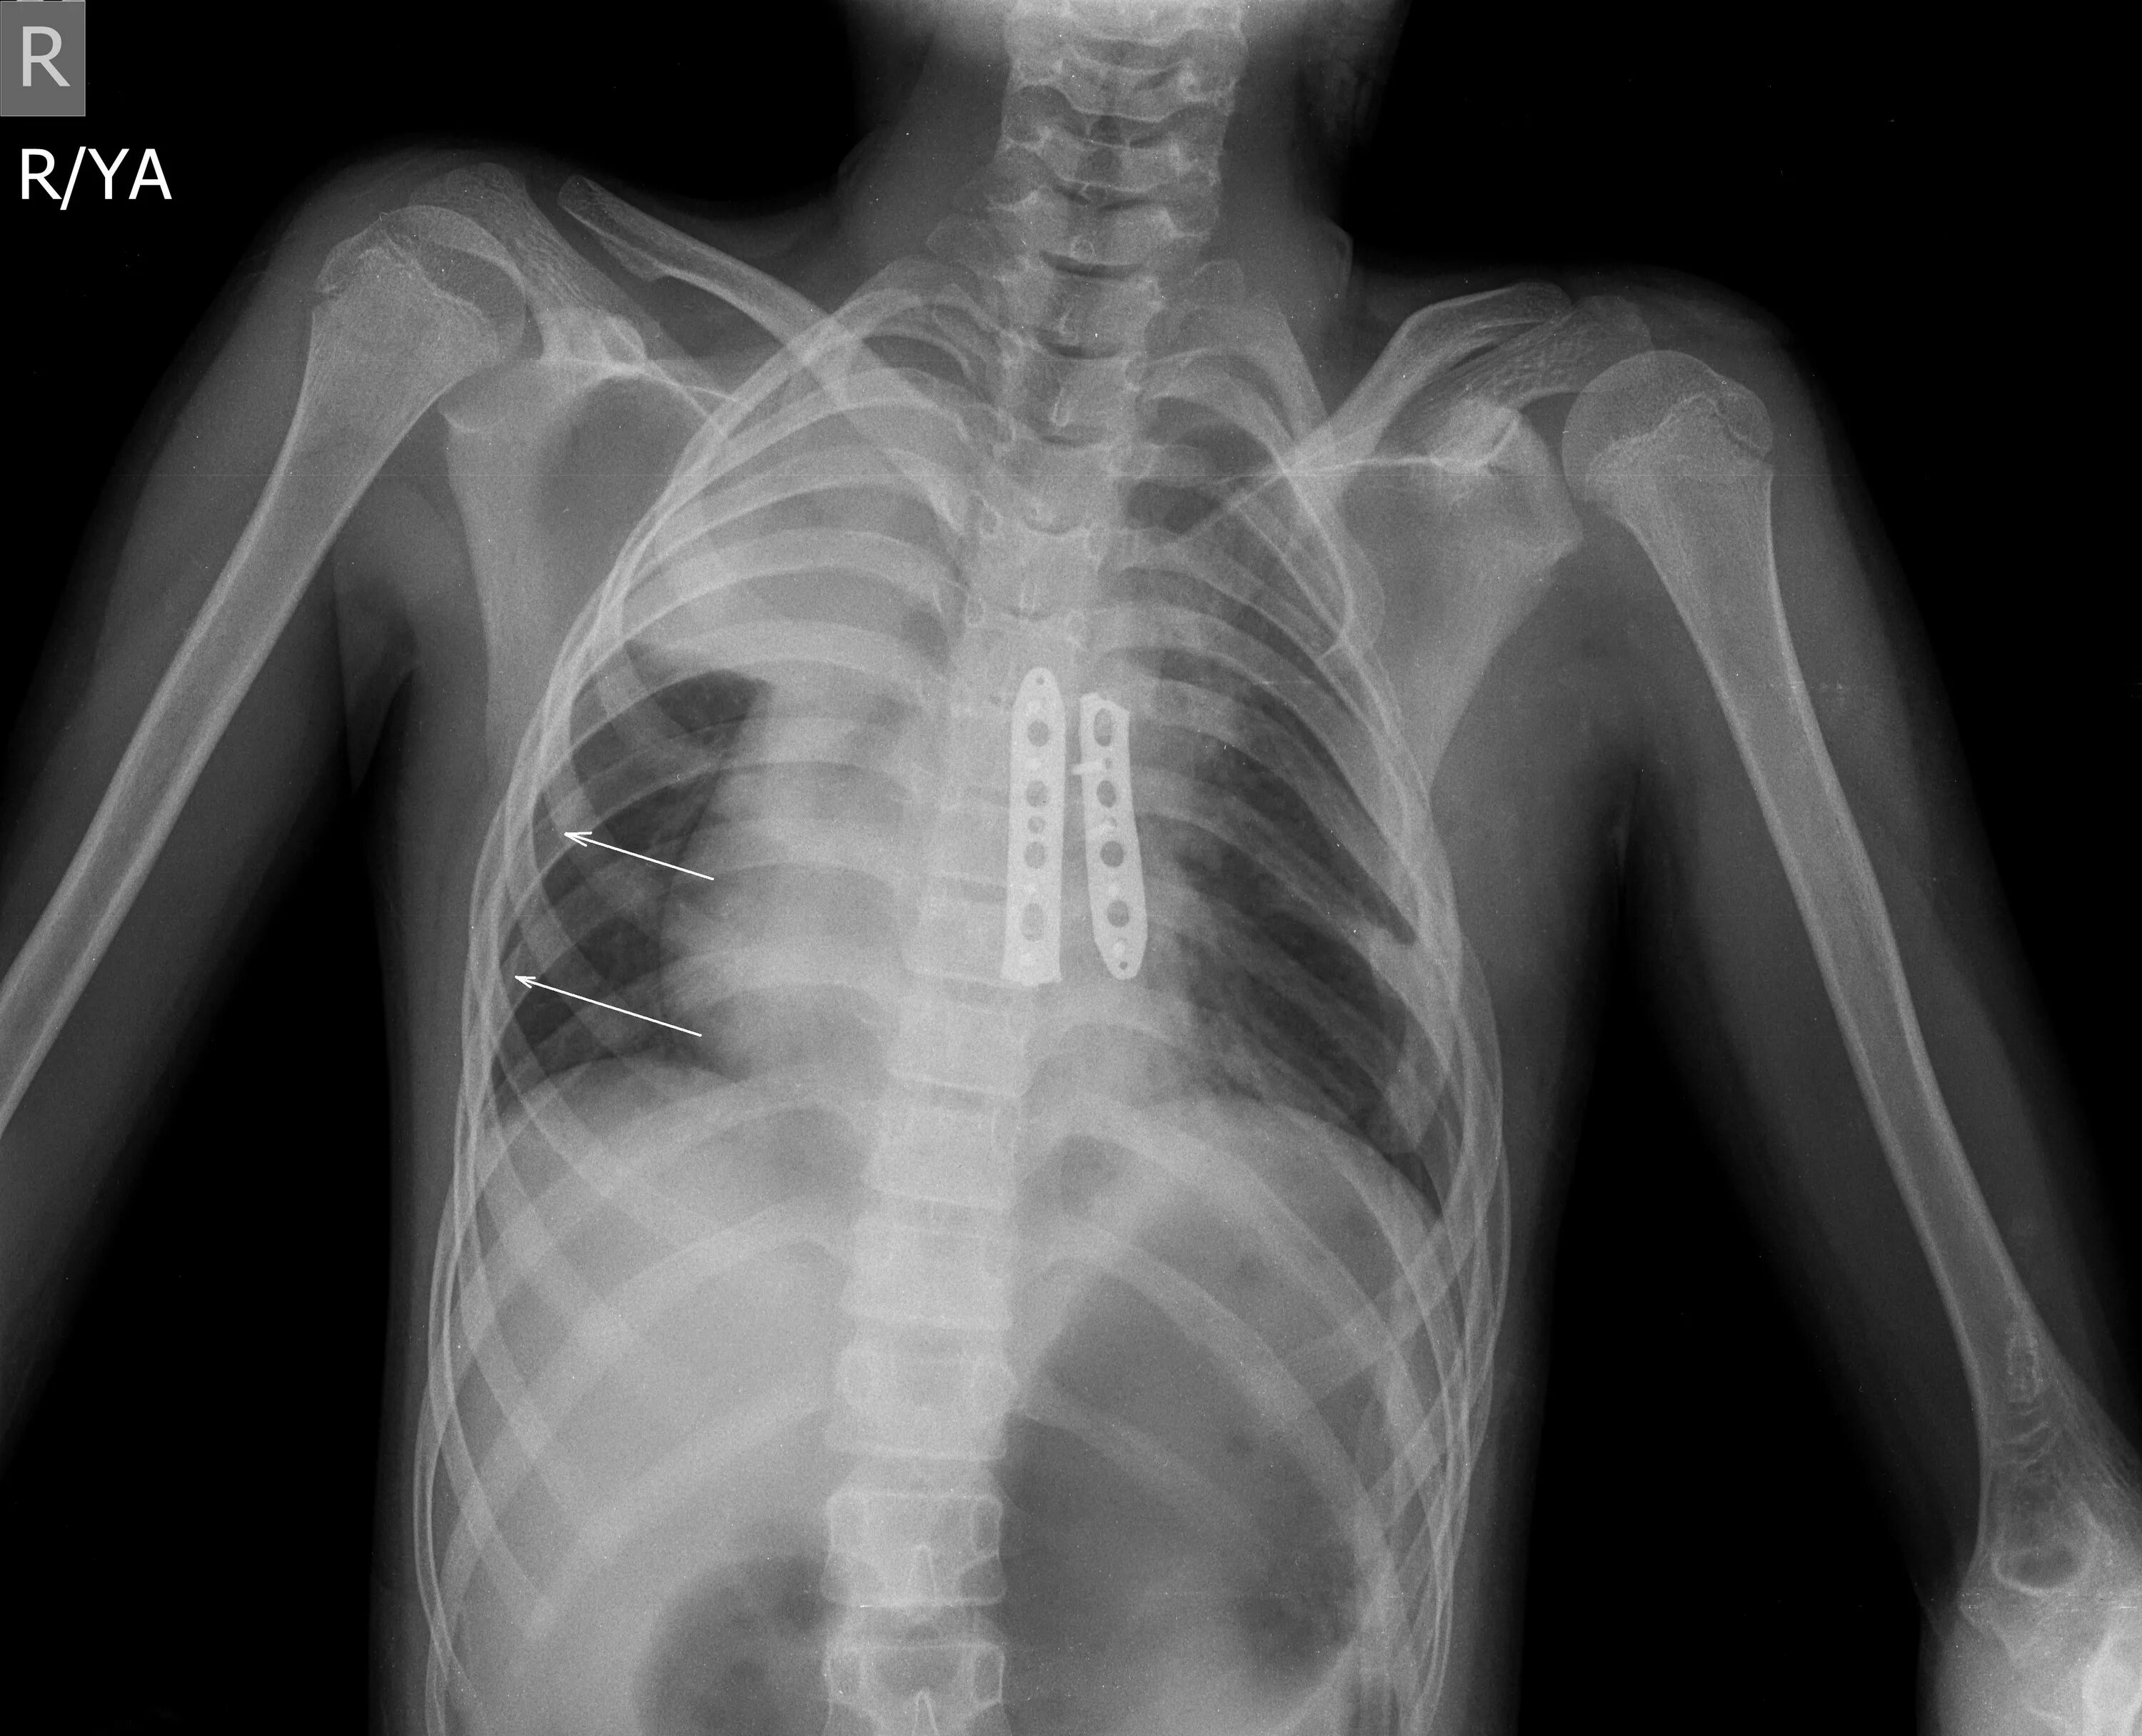

Мышечный дефект